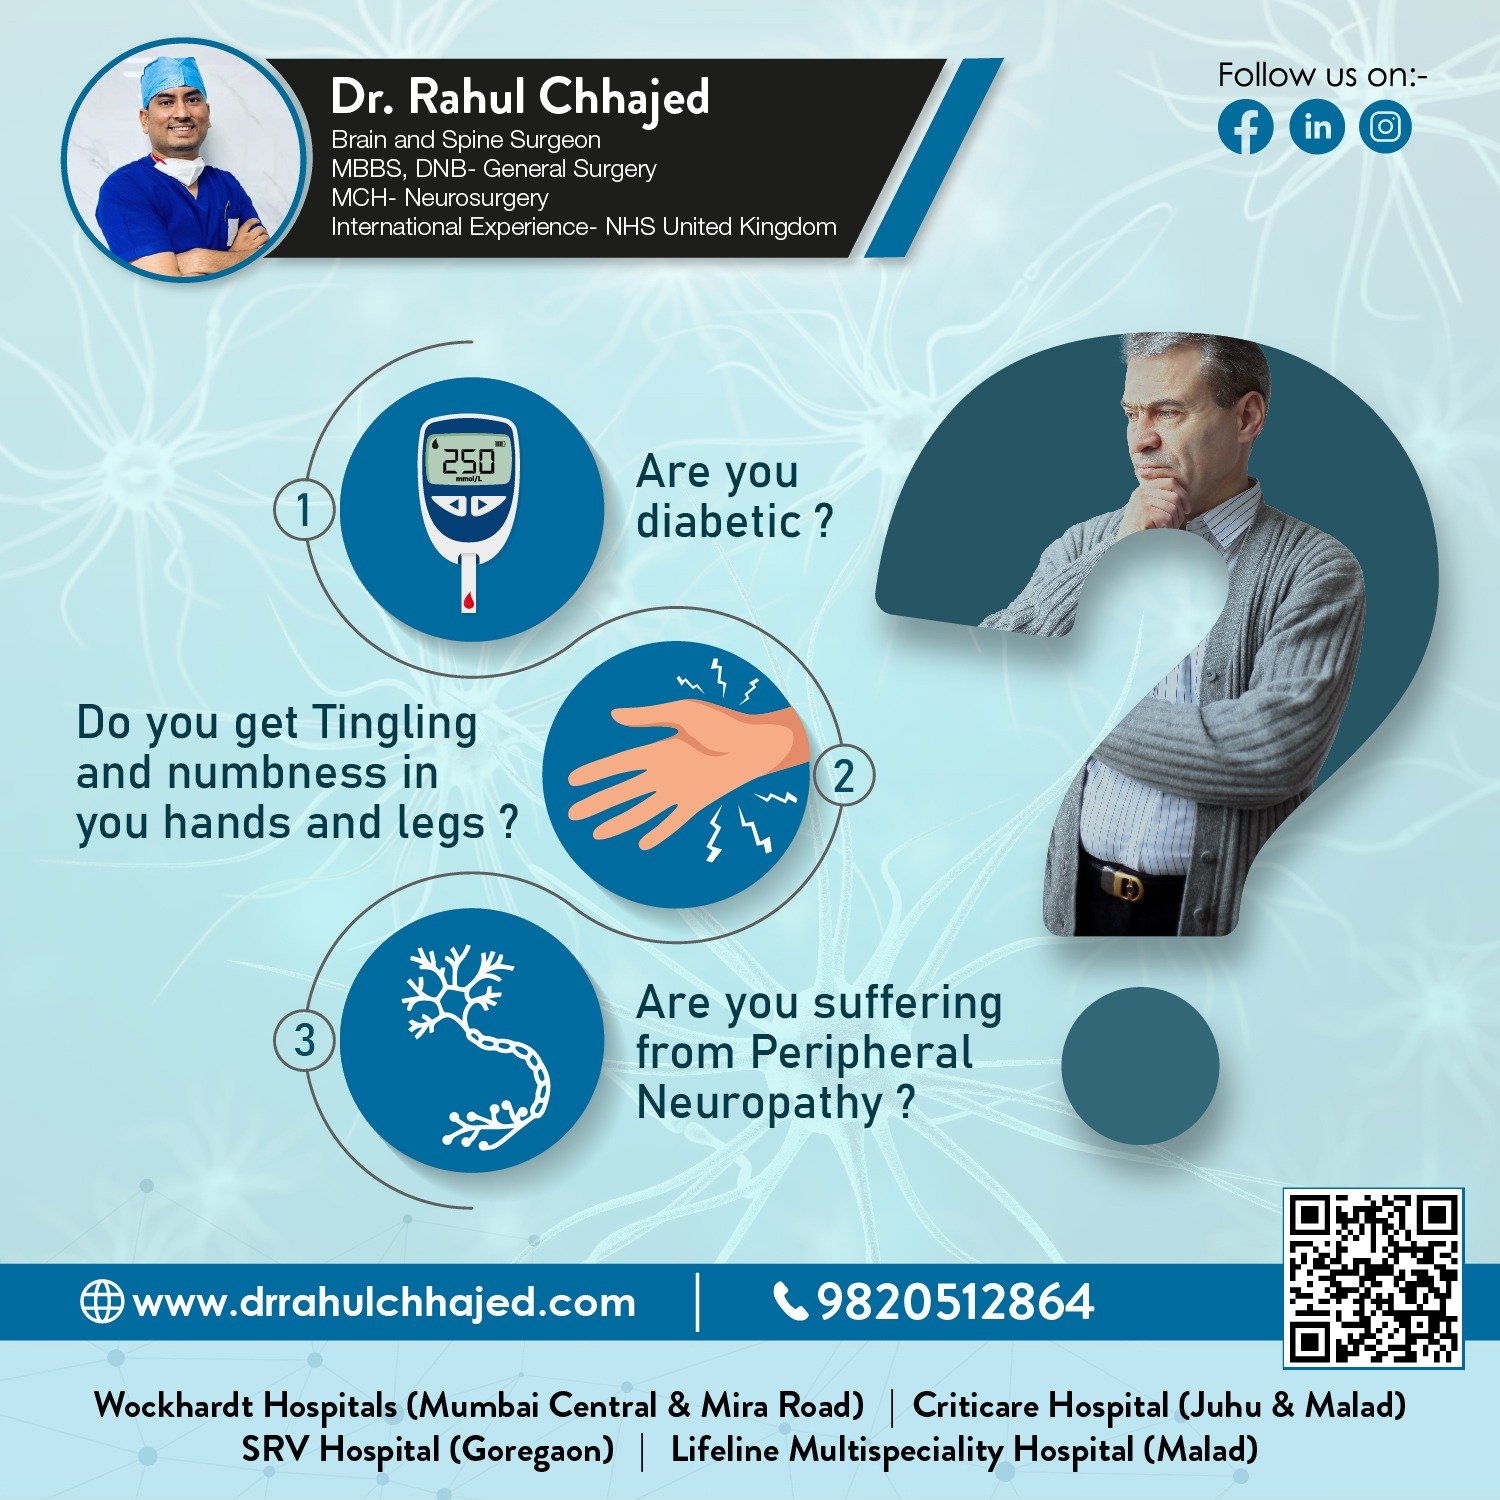

Some of the services provided by Dr. Rahul are Tumor( Cancer), Brain and Spine Trauma, Spine surgery -Minimal Invasive/ open spine surgery, Stroke patients (Paralysis), Back pain-Sciatica, Trigeminal Neuralgia and Neck Pain, Brain haemorrhage, headache-Migraine, etc

- What are the services/treatments offered by Dr. Rahul Chhajed? Dr. Rahul Chhajed is a prominent Neurosurgeon and practicing for more than 10 years. He is an expert in Stroke, Brain & Spine Surgery, Brain & Spinal tumors, Back Pain, Minimal invasive spine surgery / endoscopic spine surgery, Brain Trauma/Injuries, Stroke, Paralysis Etc.